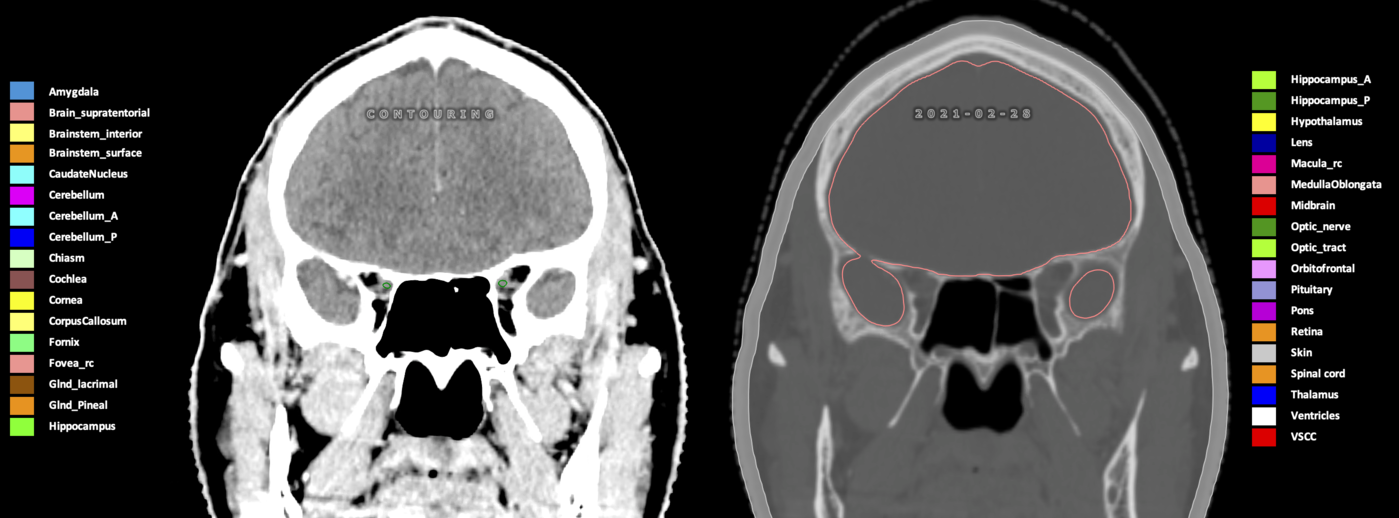

Eekers et al. have published an international neurological atlas for contouring of organs at risk in consensus with the European Particle Therapy Network (EPTN) in 2018 and an update in 2021. The purpose of this consensus atlas is to decrease inter- and intra-observer variability in delineating OARs relevant for neuro-oncology.

Included are all OARs known to be relevant for radiation-induced toxicity in neuro-oncology: brain, brainstem (midbrain, pons, medulla oblongata), chiasm, cerebellum (anterior & posterior), cochlea, cornea, hippocampus (anterior & posterior), hypothalamus, lens, lacrimal gland, optic nerve, pituitary, skin, and vestibular & semicircular canals. To further facilitate research on cognition, vision and radiological changes after irradiation of the brain, potential clinically-relevant OARs are included: amygdala, caudate nucleus, cerebellum (anterior & posterior), corpus callosum, fornix, macula, optic tract, orbitofrontal cortex, periventricular space (PVS), pineal gland, and thalamus.

Three-dimensional delineation of the 25 consensus OARs for neuro-oncology are shown on CT (WW/WL 120/40, 3000/600), 3T MR images, (T1Gd, T2FLAIR 1mm) and 7T MR (MP2RAGE 0.7 mm). All are presented in transversal, sagittal and coronal view.